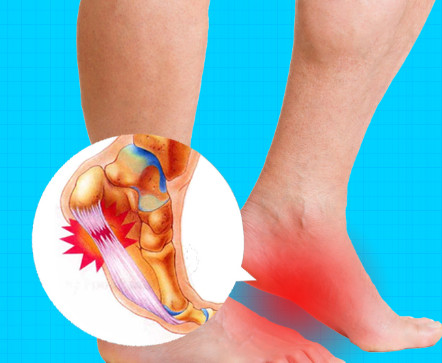

족저근막염 원인

무리한 걷기나 달리기

발에는 작은 근육이 많아 과도하게 사용하면 미세 손상이 발생합니다. 회복되지 않은 상태에서 다시 무리하면 염증이 생기고 통증으로 이어질 수 있습니다.

비만

체중이 급격히 증가하면 발바닥에 가해지는 부담이 커져 근육이 버티지 못하고 염증이 발생할 수 있습니다. 특히 출산이나 생활 변화로 체중이 늘어난 경우 주의가 필요합니다.